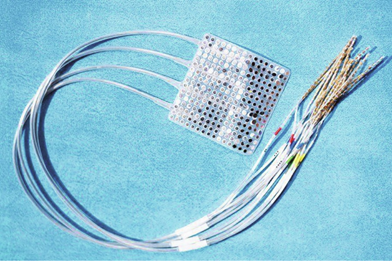

图源:BrainGate.org;BrainGate研究合作开发的BCI由100个微小的金属电极组成(大小约为一枚10美分硬币),用来记录来自大脑运动皮层和书写有关的部分信号,并将这些信号处理后在计算机上实时生成相应的文本